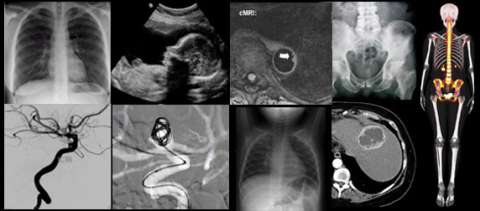

Radiologists are experts in all types of imaging, including advanced techniques.

UCLA Radiology provides the full range of diagnostic imaging services, as well as selected therapeutic techniques, on both an inpatient and outpatient basis.

Using the full range of diagnostic modalities, we offer specialized services in the following areas: